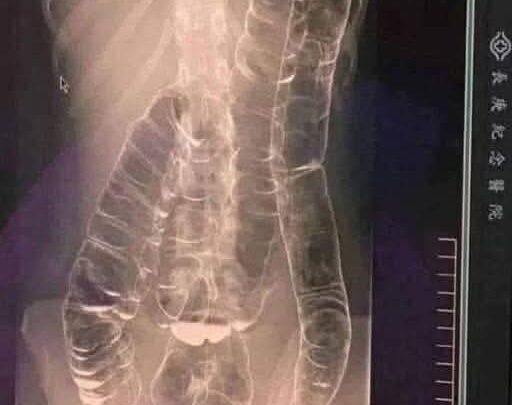

When waste accumulates in the colon due to an inefficient digestive system, it causes severe discomfort and bloating. Over time, the colon expands beyond its normal size, struggling to contain the excessive buildup of feces. In this case, medical imaging revealed a severely distended colon that had enlarged so much it reached up toward the chest,

dangerously close to the heart. The stretching had nearly erased the colon’s natural folds and wrinkles, essential for its proper function. Left untreated, this condition could have led to life-threatening complications.